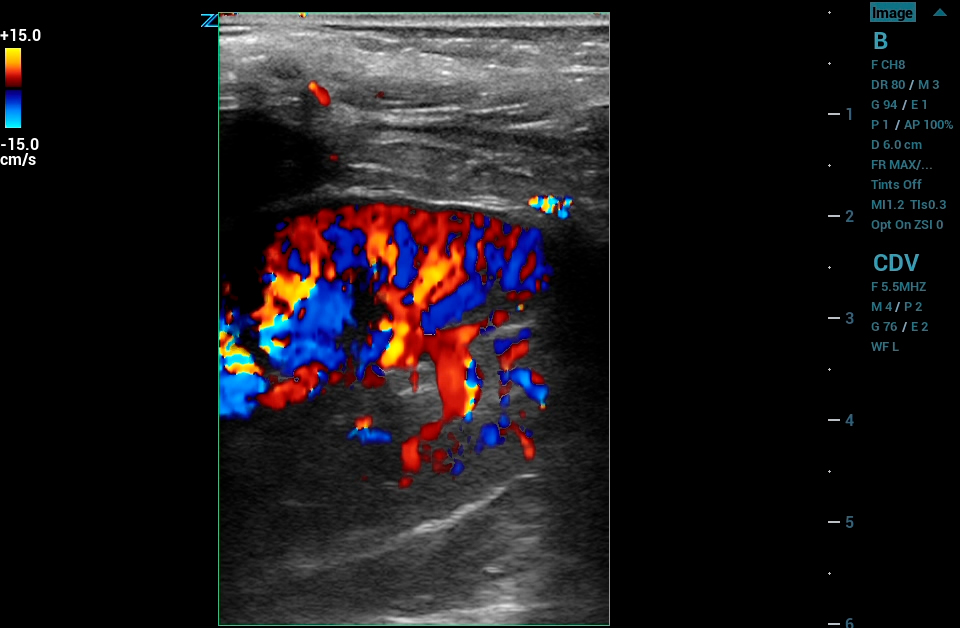

ARFI

ARFI Elastography* with quantification is a non-invasive method of assessing liver tissue stiffness. Using real time imaging as a guide, ARFI automatically calculates liver tissue stiffness values (AVG, MEAN, and IQR) for a predetermined region of interest. Multiple samples can be recorded and displayed in a report.

* Available on the C4-1 transducer